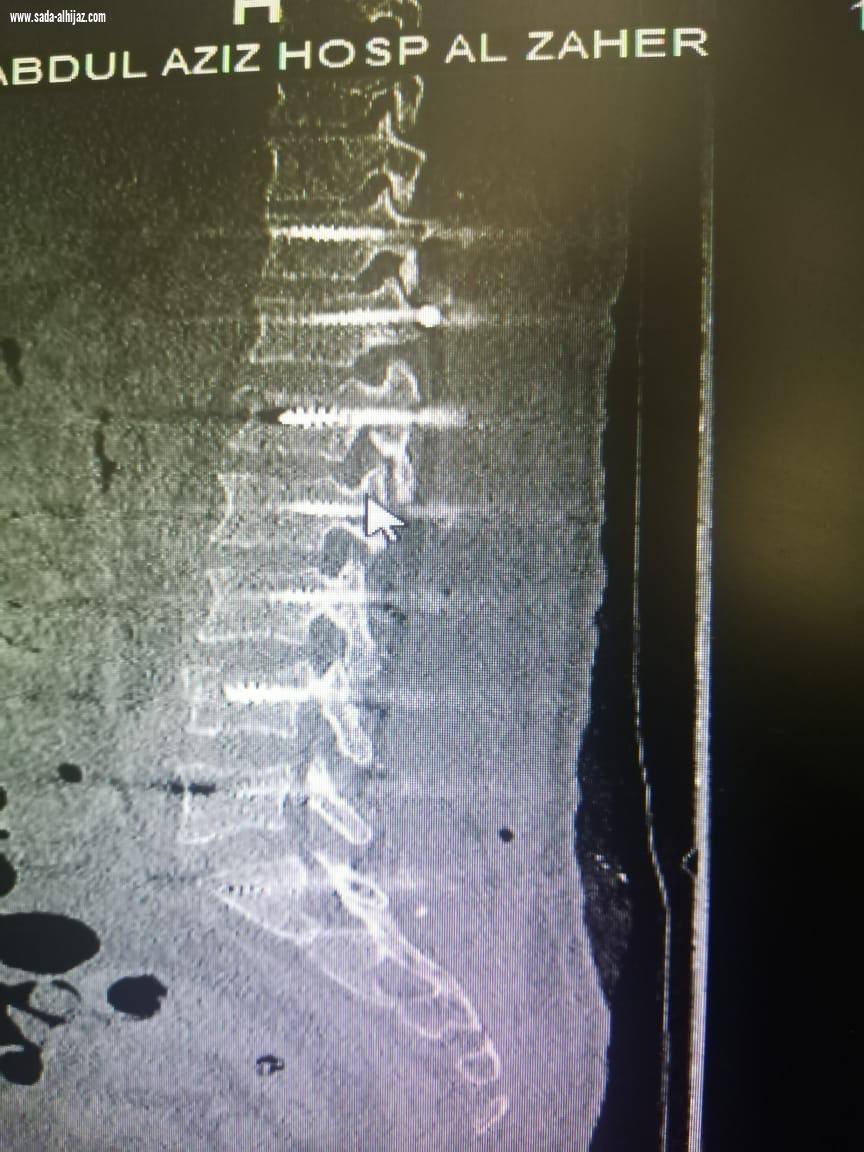

عبدالعزيزالنفيعي- الطائف تمكن فريق طبي بمستشفى الملك عبدالعزيز عضو التجمع الصحي بمكة بقسم جراحة المخ والأعصاب من إنقاذ حياة رجل يبلغ من العمر ( 30) تعرض لسقوط من الدور الخامس من إحدى البنايات بالعاصمة المقدسة . واوضح رئيس قسم جراحة المخ والاعصاب الدكتور زهير برناوي ان المصاب حضر إلى قسم الطوارئ بالمستشفى وهو يعاني من كسر مضاعف بالفقرة القطنية الاولى وكسر منضغط بالفقرة القطنية الرابعة وانزلاق غضروفي حاد بين الفقرتين الثانية والثالثة القطنية ونتج عن ذلك شلل نصفي وعدم التحكم بالإخراج وبعد عمل الاشعات والفحوصات اللازمة وعلى إثره دخل إلى غرفة العمليات، كحاله طارئة وتم اجراء عملية تثبيت للفقرات من الناحية الصدريه رقم ١١ وحتى العجزية رقم ١ مروراً بكل الفقرات القطنية الخمسة مع استئصال الغضروفي استغرقت العملية ( 8 ) ساعات وتم تنويم المصاب بالعناية المركزة لمدة يومين بقيادة استشاري جراحة المخ والاعصاب الدكتور محمد مرسي المشد وبفضل من الله تكللت العملية - بالنجاح، حيث تم نقل المصاب إلى قسم التنويم وخضع لعلاج دوائي وطبيعي الى ان استطاع السير على قدمية وهو بحالة مستقرة وتم خروجه من المستشفى.